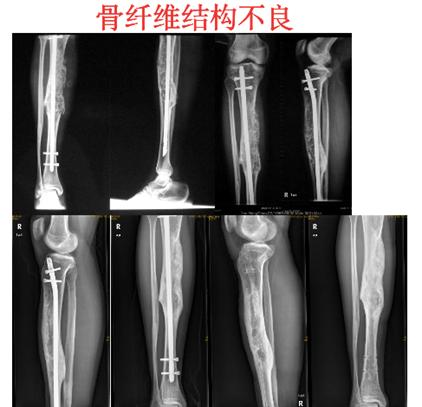

转移性骨肿瘤常见来源有:乳腺癌、前列腺癌、肺癌、甲状腺癌、肾癌。还有类肿瘤性的其他病损,包括骨囊肿、动脉瘤样骨囊肿、嗜酸性肉芽肿、骨纤维结构不良。其中青少年好发的恶性肿瘤最常见的是骨肉瘤、尤文肉瘤。